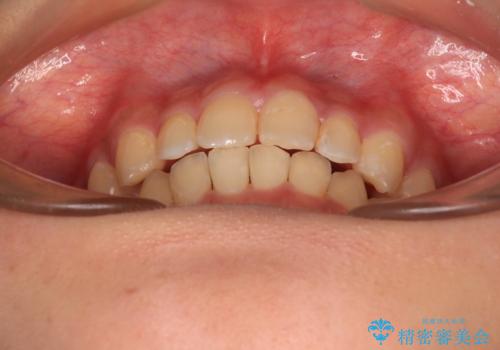

- 前歯のデコボコと深い咬み合わせを改善したいとのことで来院された患者様です。

奥歯の咬み合わせは上顎に対して下顎が後方位にあり、上顎前歯で下顎前歯が隠れるような典型的な過蓋咬合です。

補助装置を用いて上顎大臼歯を後方に移動させながら、ワイヤー装置で歯列を整えて深い咬み合わせを挙上することとしました。